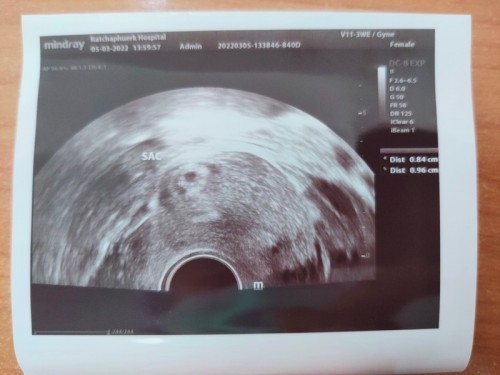

ตอนนี้เค้าได้ 6+3 รอซาวพรุ้งนี้ ตื่นเต้น รอบก่อนซาวด์ตอน4w เห็นแค่ถุงตั้งครรภ์#ขอบคุณล่วงหน้านะคะ #คุณแม่ๆช่วยแนะนำหน่อยค่ะ

บ้านนี้เจอตอน6w3d ซาวด์ผ่านช่องคลอดค่ะ เจอตัวน้อง ได้ยินเสียงหัวใจชัดเลยค่ะ